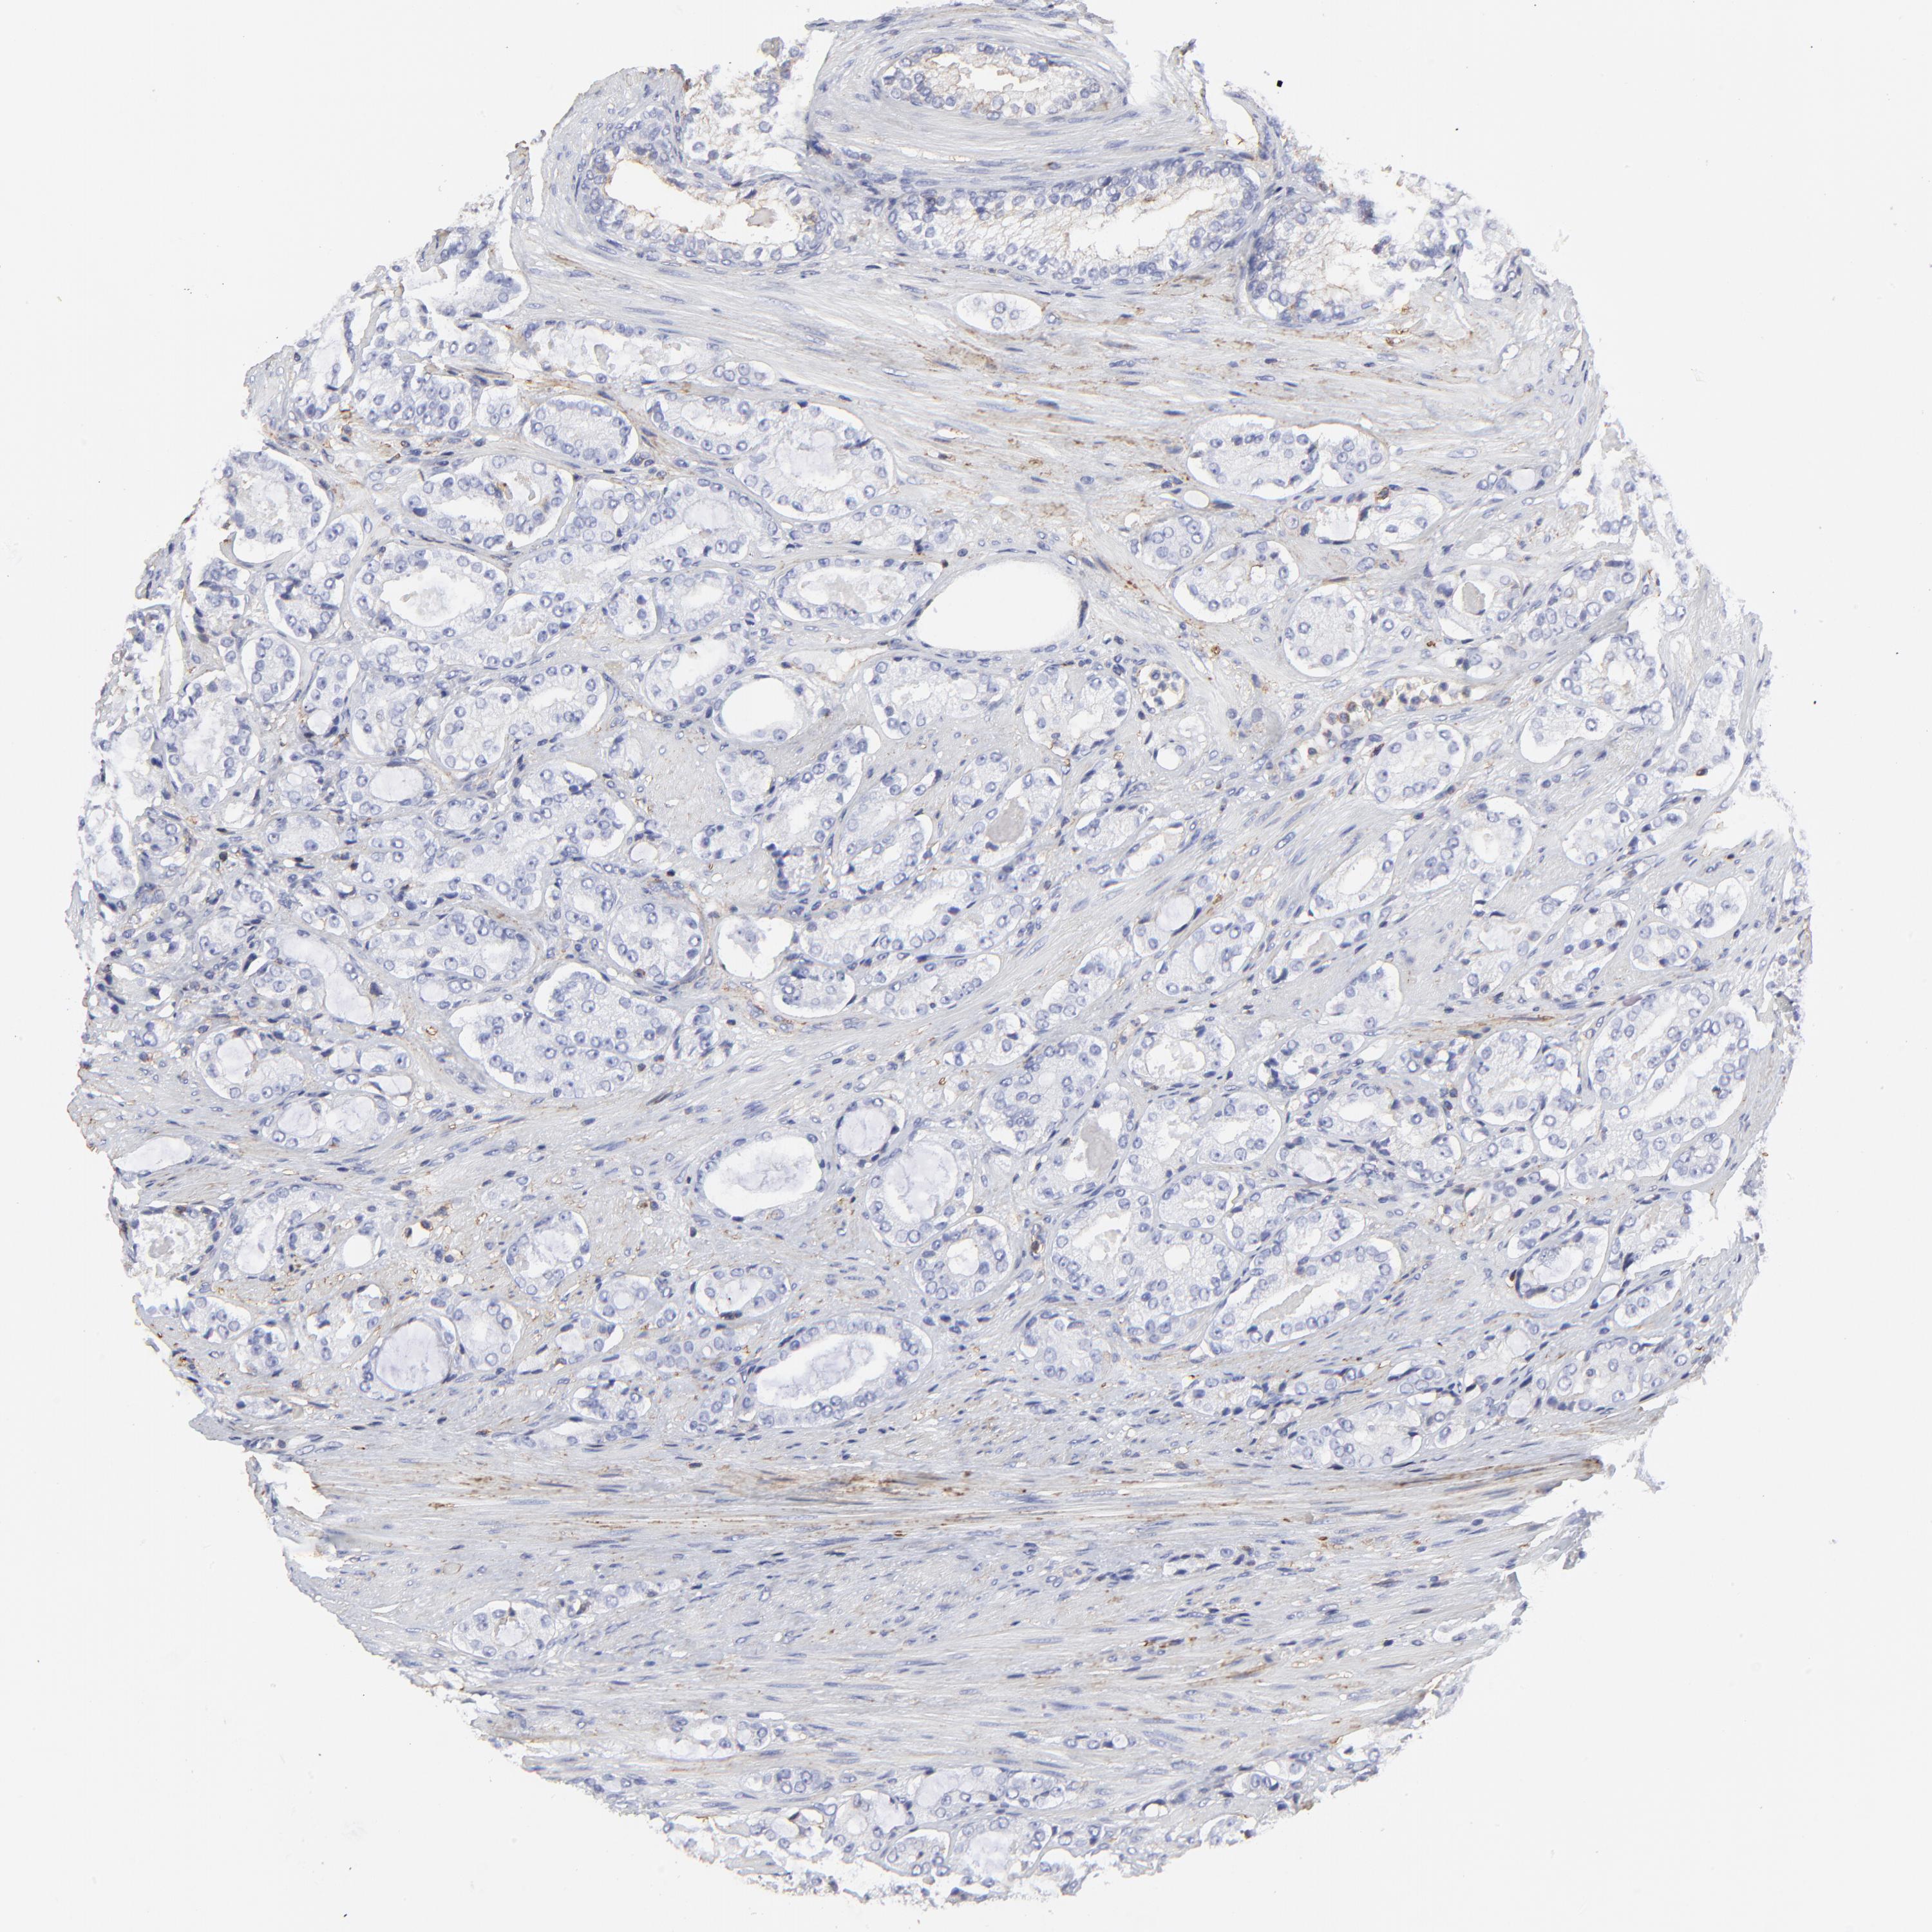

PROSTATE CANCER - Protein expressioni

A mouse-over function shows sample information and annotation data. Click on an image to view it in a full screen mode. Samples can be filtered based on level of antibody staining by selecting one or several of the following categories: high, medium, low and not detected. The assay and annotation is described here.

Note that samples used for immunohistochemistry by the Human Protein Atlas do not correspond to samples in the TCGA dataset.

Antibody stainingi

Antibody staining in the annotated cell types in the current human tissue is reported as not detected, low, medium, or high, based on conventional immunohistochemistry profiling in selected tissues. This score is based on the combination of the staining intensity and fraction of stained cells.

Each image is clickable and will lead to virtual microscopy that enables deeper exploration of all samples and also displays staining intensity scores, fraction scores and subcellular localization as well as patient and tissue information for each sample.

Antibody HPA002462

Antibody HPA009650

Antibody CAB005077

Staining

High

Medium

Low

Not detected

Intensity

Strong

Moderate

Weak

Negative

Quantity

>75%

75%-25%

<25%

None

Location

Nuclear

Cytoplasmic/membranous

Cytoplasmic/membranous,nuclear

Adenocarcinoma, Low grade

Adenocarcinoma, High grade